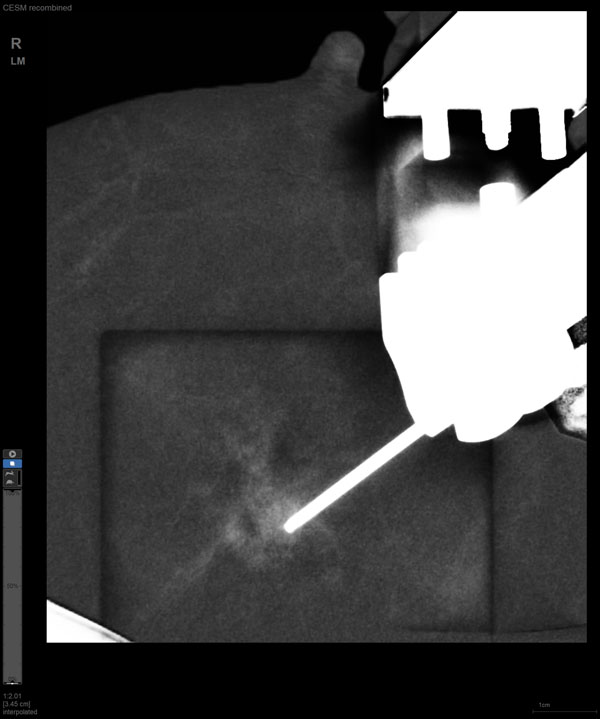

某患者增强磁共振成像MRI显示肿瘤周边有活性,中心区域有组织坏死。为得到准确的病理结果,穿刺靶区需避开肿物坏死区域。在与患者主管医生充分讨论后,放射科医生为患者行CEM引导下穿刺活检术。术中,CEM检查肿物同样显示为环形强化,巧妙避开坏死区域后,穿刺靶区选择了肿物增强早期明显强化区域,术程顺利,仅用时15分钟。术后该患者病理结果为浸润性导管癌Ⅱ级。

CEM作为近年来新兴的乳腺成像方法,是在传统乳腺X线摄影的基础上,通过静脉注射碘对比剂,用高低两种能量的X线摄影通过计算机进行能量减影处理,得到的减影像能突出显示病灶强化特征的一项新技术。其优势在于,既能显示乳腺病变的形态学特征,又能反映病变新生血管的血供情况,被越来越多地应用于临床。

随着计算机技术发展和乳腺X线机硬件的提升,CEM与立体定向活检技术相结合的CEM引导下穿刺活检术开始在临床应用。与MRI引导的乳腺穿刺活检相比,CEM穿刺活检无需抗核磁耗材,成本更低,检查速度更快。据国外研究文献报道,CEM引导的穿刺活检有可能成为MRI引导的乳腺穿刺活检的有效替代方案。